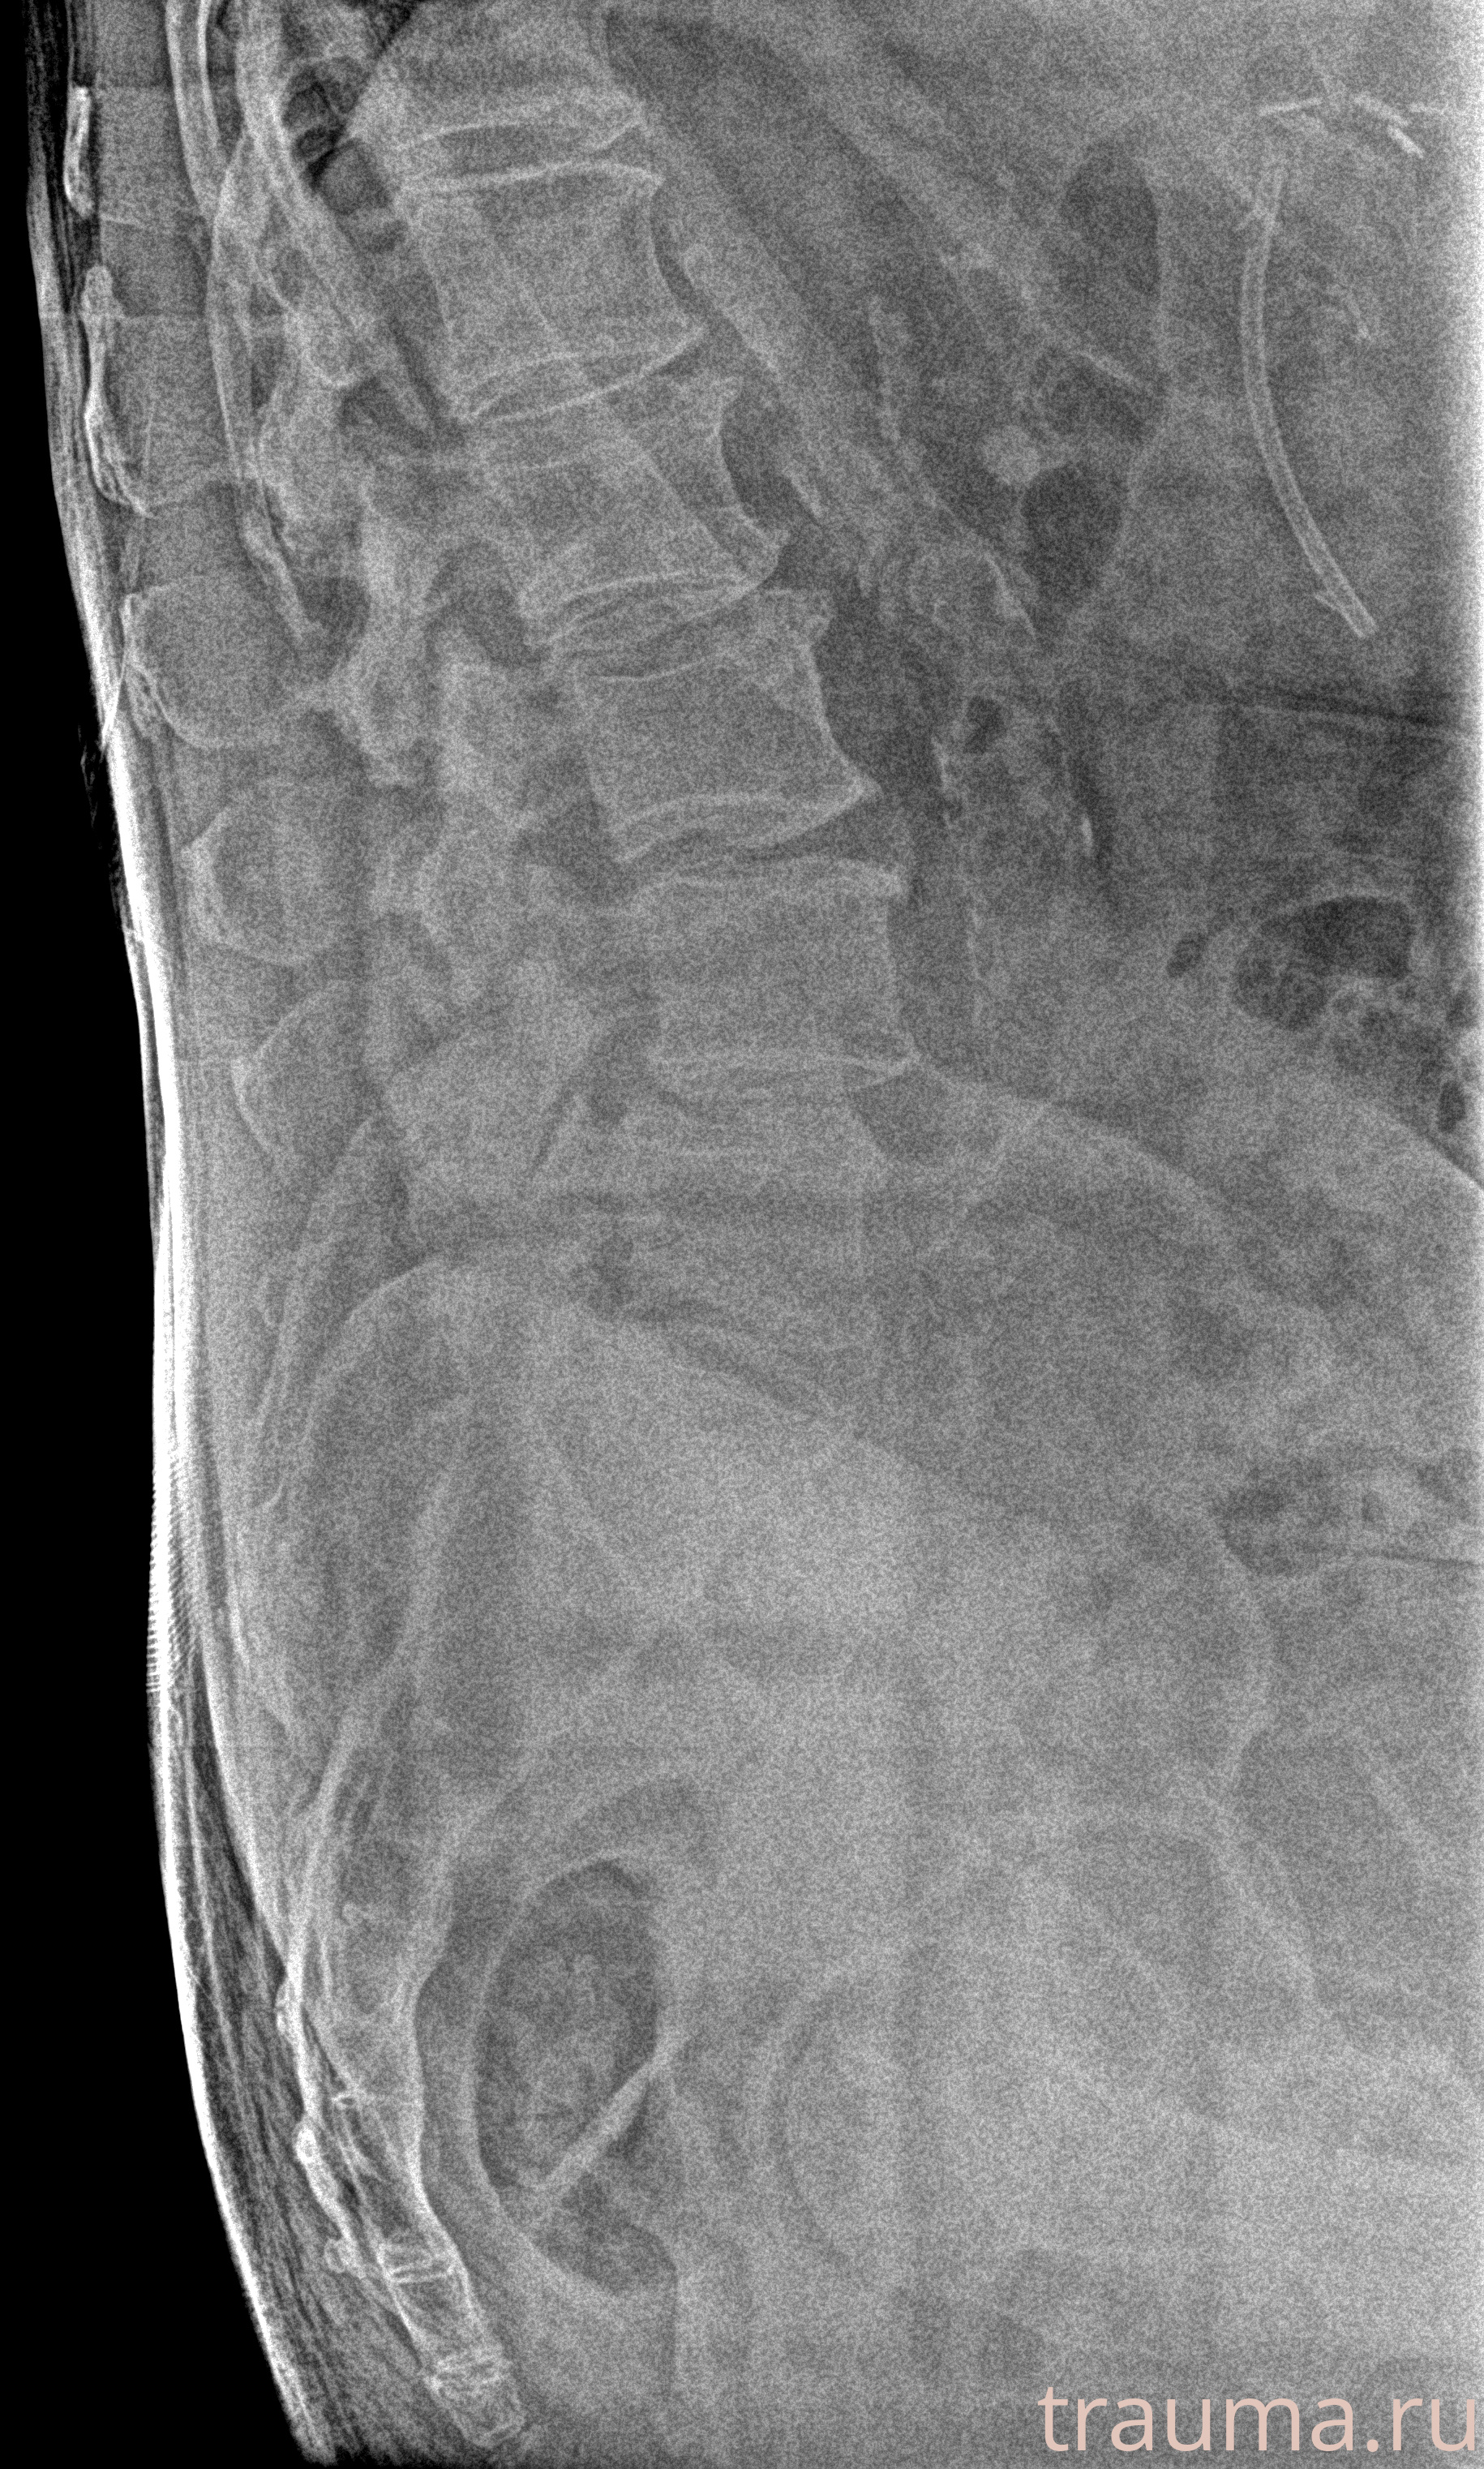

Рентгенограммы

Рентген на дому: по вашему адресу приезжает врач-рентгенолог, травматолог-ортопед с мобильным рентгеновским аппаратом, проводит диагностику травмы или заболевания, делает необходимые рентгенограммы, дает рекомендации по дальнейшему лечению. Получить качественные снимки в домашних условиях возможно благодаря уникальной методике, разработанной МосРентген Центром для института  Склифосовского